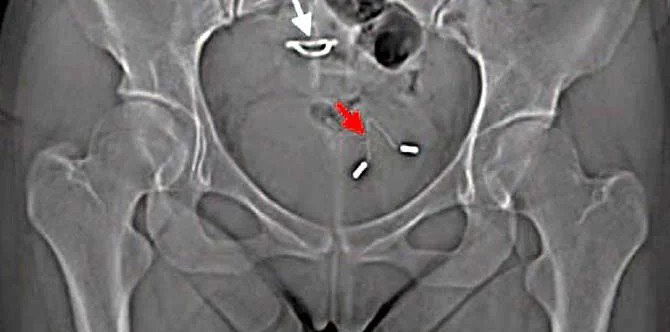

They then performed an X-ray and the findings were shocking!

The X-ray revealed that the IUD had punctured her uterus and moved to her bladder.

What happened to her is an example of uterine perforation that happens to approximately one in every 1000 women who uses an IUD, the Medical report stated. It isn’t common but it can and does happen.